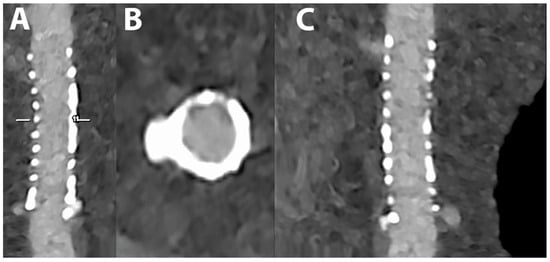

5.4. Coronary Artery Stenting

- Mannil, M.; Hickethier, T.; von Spiczak, J.; Baer, M.; Henning, A.; Hertel, M.; Schmidt, B.; Flohr, T.; Maintz, D.; Alkadhi, H. Photon-Counting CT: High-Resolution Imaging of Coronary Stents. Investig. Radiol. 2018, 53, 143–149. [Google Scholar] [CrossRef]

- Symons, R.; De Bruecker, Y.; Roosen, J.; Van Camp, L.; Cork, T.E.; Kappler, S.; Ulzheimer, S.; Sandfort, V.; Bluemke, D.A.; Pourmorteza, A. Quarter-millimeter spectral coronary stent imaging with photon-counting CT: Initial experience. J. Cardiovasc. Comput. Tomogr. 2018, 12, 509–515. [Google Scholar] [CrossRef] [PubMed]

- von Spiczak, J.; Mannil, M.; Peters, B.; Hickethier, T.; Baer, M.; Henning, A.; Schmidt, B.; Flohr, T.; Manka, R.; Maintz, D.; et al. Photon Counting Computed Tomography With Dedicated Sharp Convolution Kernels: Tapping the Potential of a New Technology for Stent Imaging. Investig. Radiol. 2018, 53, 486–494. [Google Scholar] [CrossRef] [PubMed]

- Rajagopal, J.R.; Farhadi, F.; Richards, T.; Nikpanah, M.; Sahbaee, P.; Shanbhag, S.M.; Bandettini, W.P.; Saboury, B.; Malayeri, A.A.; Pritchard, W.F.; et al. Evaluation of Coronary Plaques and Stents with Conventional and Photon-counting CT: Benefits of High-Resolution Photon-counting CT. Radiol. Cardiothorac. Imaging 2021, 3, e210102. [Google Scholar] [CrossRef] [PubMed]